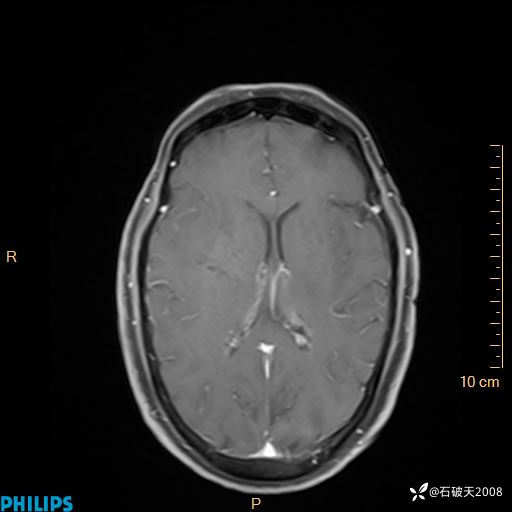

增强轴位

2024.2.21MR